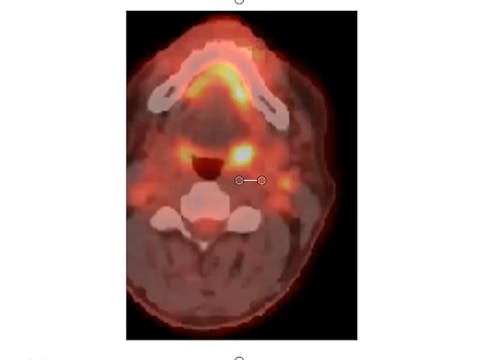

06/15/2021 - Dr. Kenneth Hu - Radiation Oncology - Head and Neck

Neck mass carcinoma, unknown primary, tonsillectomy, neck dissection and rapid lymph node regrowth, dose, treatment fields, de-escalation for HPV